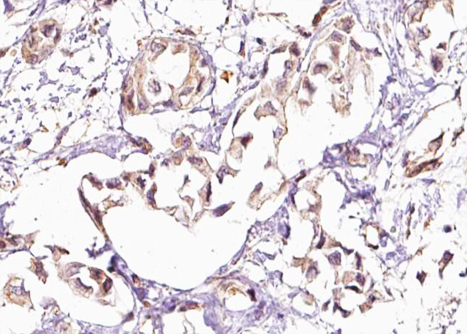

IHC (Immunohistochemistry)

(AAA326207 at 1/100 staining Human breast cancer tissue by IHC-P. The sample was formaldehyde fixed and a heat mediated antigen retrieval step in citrate buffer was performed. The sample was then blocked and incubated with the antibody for 1.5 hours at 22 degree C. An HRP conjugated goat anti-rabbit antibody was used as the secondary.)